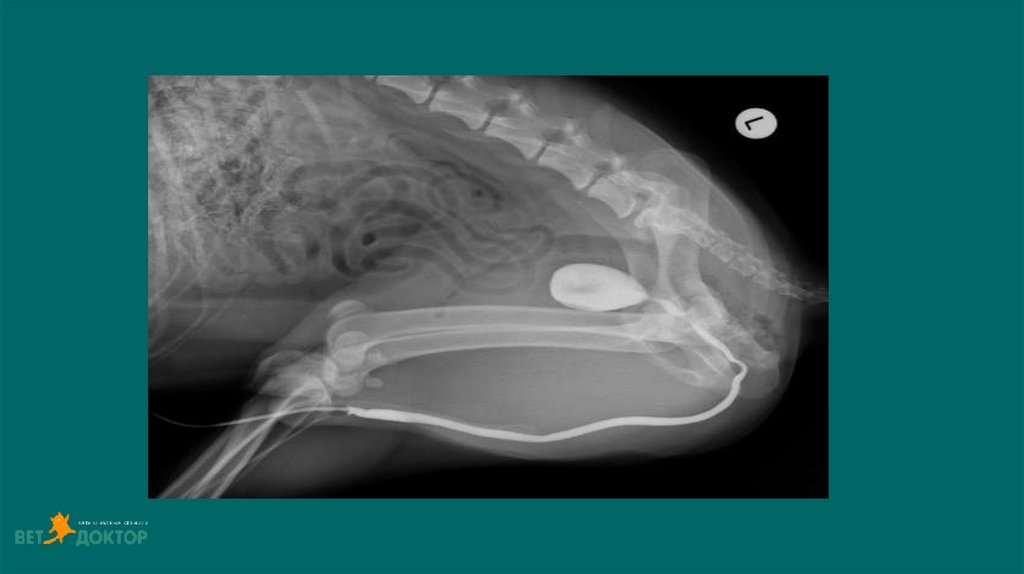

13. Позитивно-контрастная цистоуретрограмма

Показания:

Определение размера, формы и расположения мочевого пузыря

Определение проходимости или разрыва мочевого пузыря или уретры.

Обнаружение дефектов наполнения, связанных с уролитами (цистины/ураты) или гематомами,

выявления полипов или новообразований.

ПОДГОТОВКА

• Установка стерильного мочевого катетера для введения контраста

• Получение обзорных боковых и ВД снимков

• Введение стерильного йодсодержащего контраста в расчете 10мл/кг( разбавлен стерильным

физ.раствором 1:2 или 1:5)

• Выполняем латеральные/ВД снимки немедленно после введения контраста .

• Для получения уретрограммы оттянуть дистально катетер, ввести контраст одновременно сделать

боковой снимок ,провести серию снимков.

• Удаление контраста из мочевого пузыря по завершению